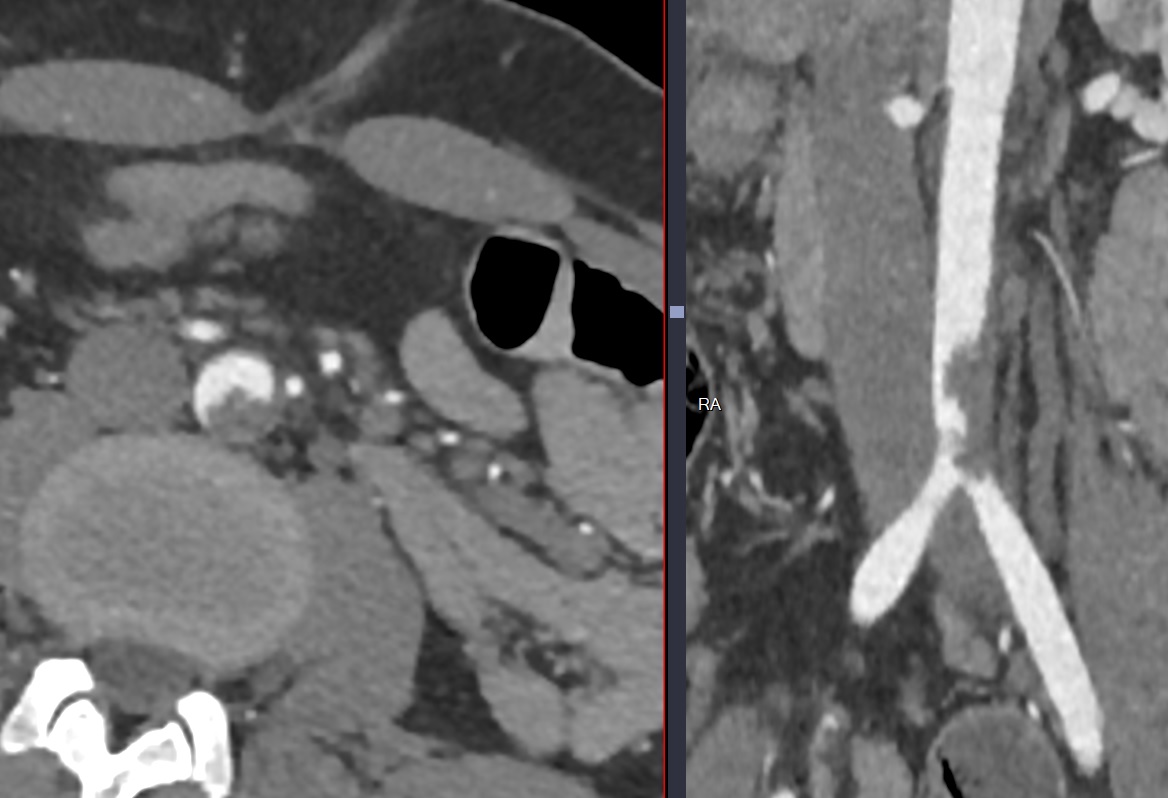

Thrombus Flottant Artériel

Thrombus flottant aortique